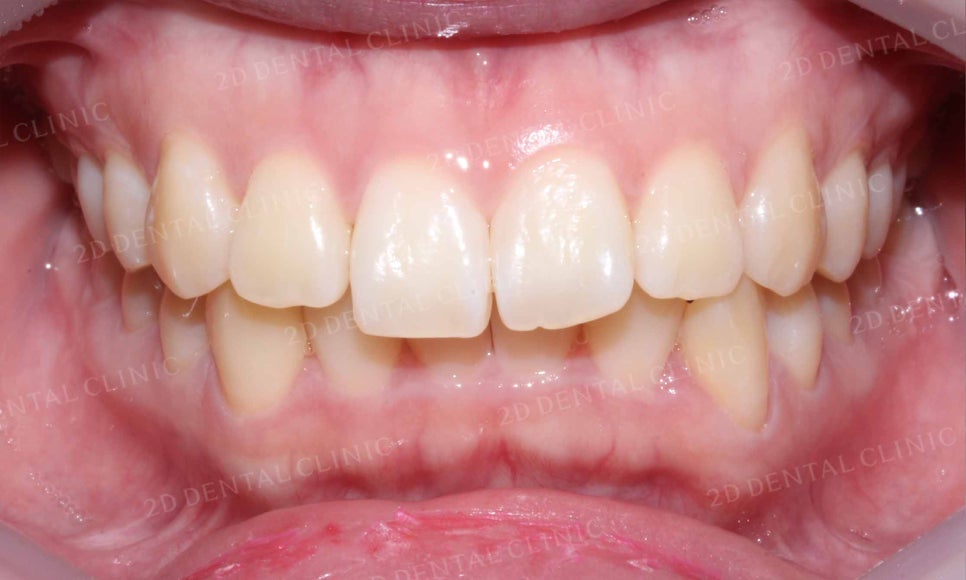

전체적인 치열을 보시면 토끼앞니 교정 전

윗니에 의해 아랫니가 과도하게 많이 덮이고

상악과 하악의 크기도 부조화스러운 모습이었는데요,

교정 후 '과개교합' 증상이 사라지고

상하악의 크기도 조화롭게 바뀐 모습입니다.

앞니의 뻐드러짐이 잘 나타나던 윗니 또한

토끼 앞니 교정 후 틀어졌던 치열이 가지런하게 바뀌고

밖으로 뻗어있던 앞니도 정상적인 각도로 교정된 모습이네요~